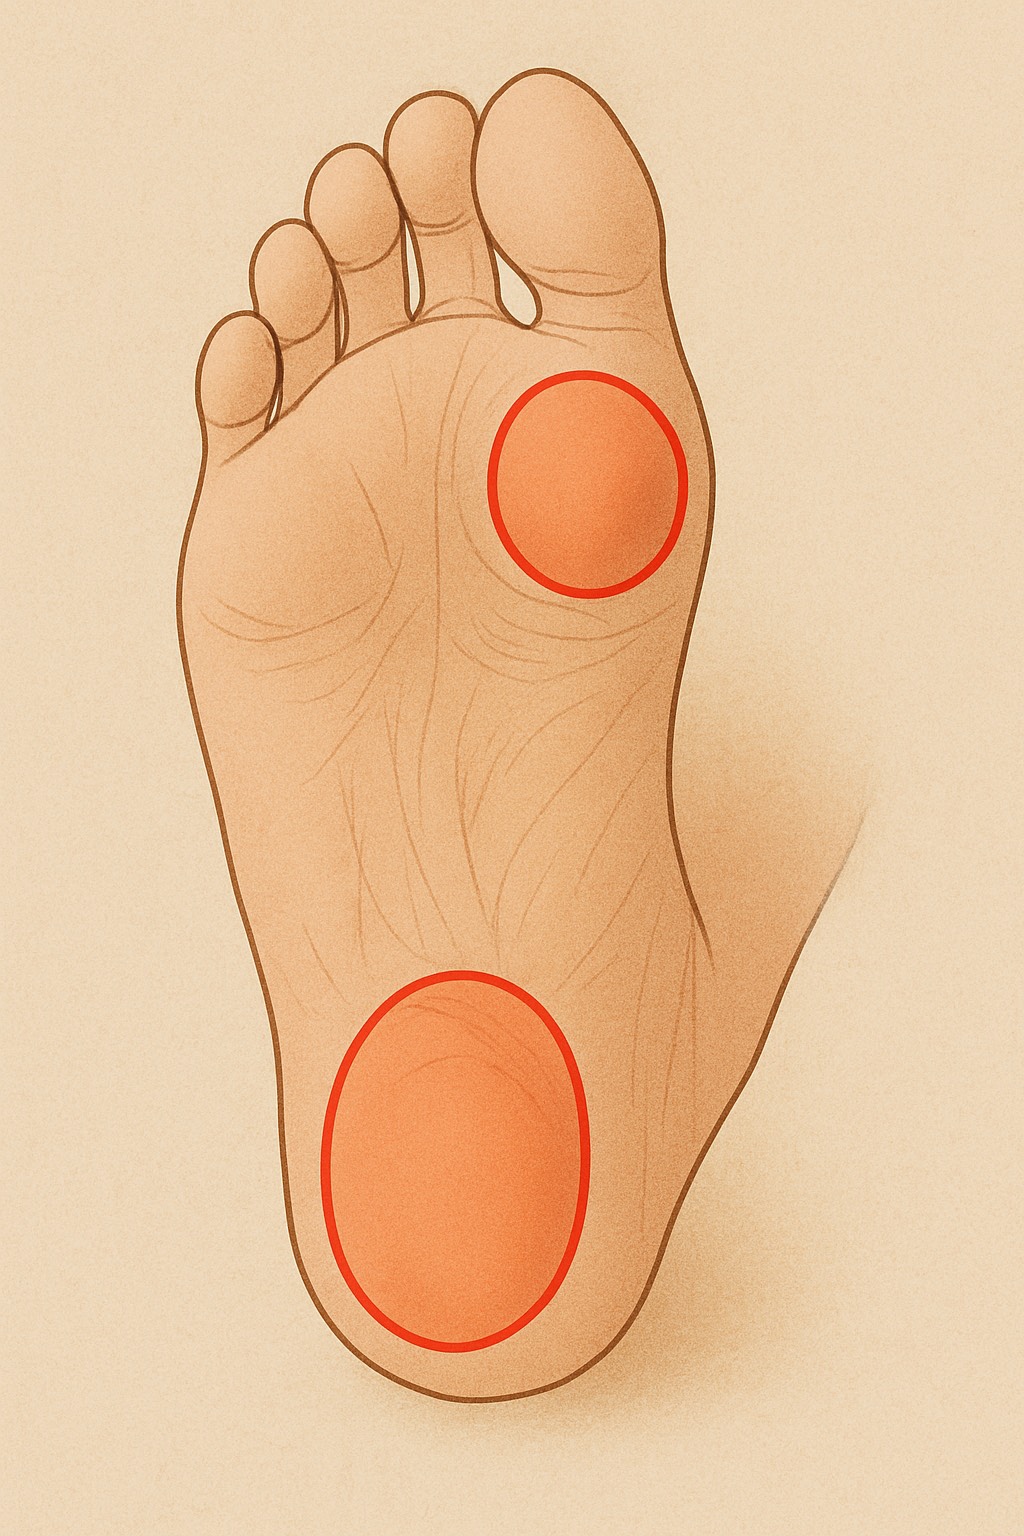

アキレス腱の炎症は主に2つの部位に分けられます。

1.アキレス腱の中央部(腱の真ん中あたり)

・ふくらはぎと踵のちょうど間、腱の途中に炎症が起きるタイプ

2.アキレス腱付着部(かかとの骨に近い部分)

・踵の少し上、腱が骨にくっつく部分に炎症が出るタイプ